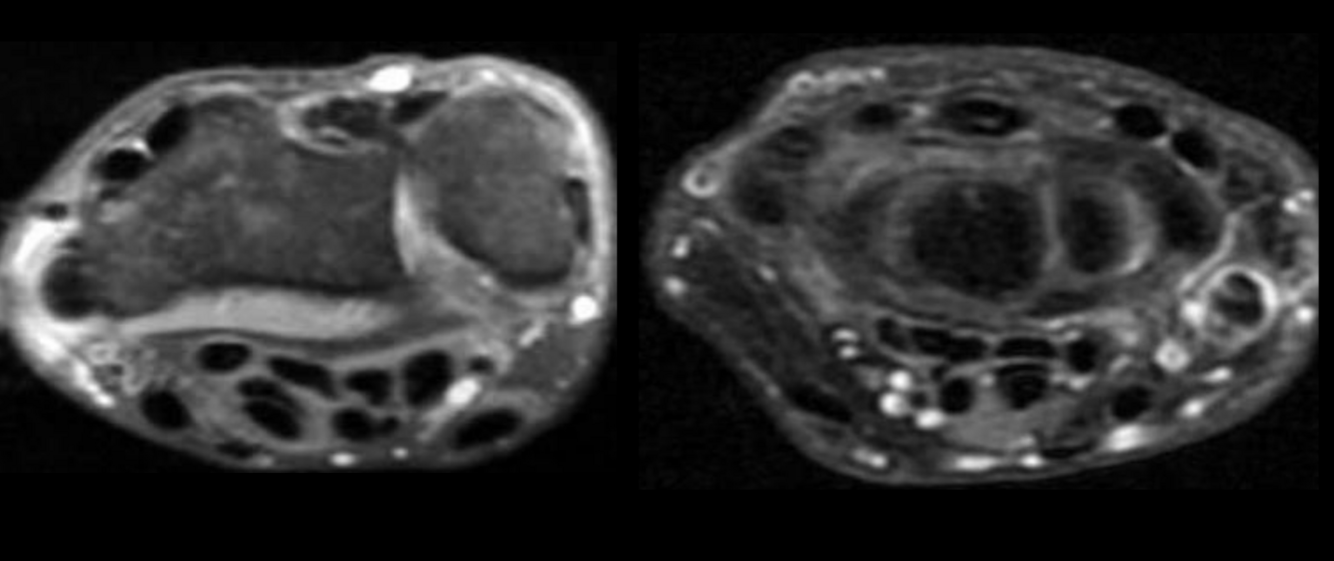

RM Sx Tunel del Carpo

Nervio aplanádo hiperintenso

Captación de contraste